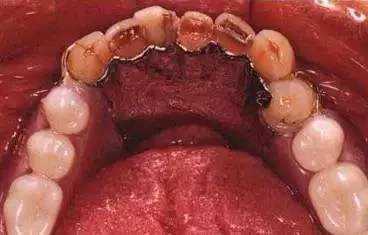

目前前牙固定方法最常用的是结扎丝联合光固化树脂的牙周夹板法,即用结扎丝将患牙与邻近健康牙连续结扎,再用光固化树脂贴面,以固定尼龙丝并恢复前牙外观。

经此方法固定后,患牙不仅得到固定,而且外形、色泽方面较以往更为美观。后牙松动更多地采用修复的方法进行固定,如铸造连续卡环夹板固定法,或连续冠、连续嵌体等,经修复法固定后,患牙能够承受较大的合力,功能恢复颇佳。此外,个别松动牙还可以不依赖邻近健康牙而采取根管内种植术,也可取得良好的固定效果。